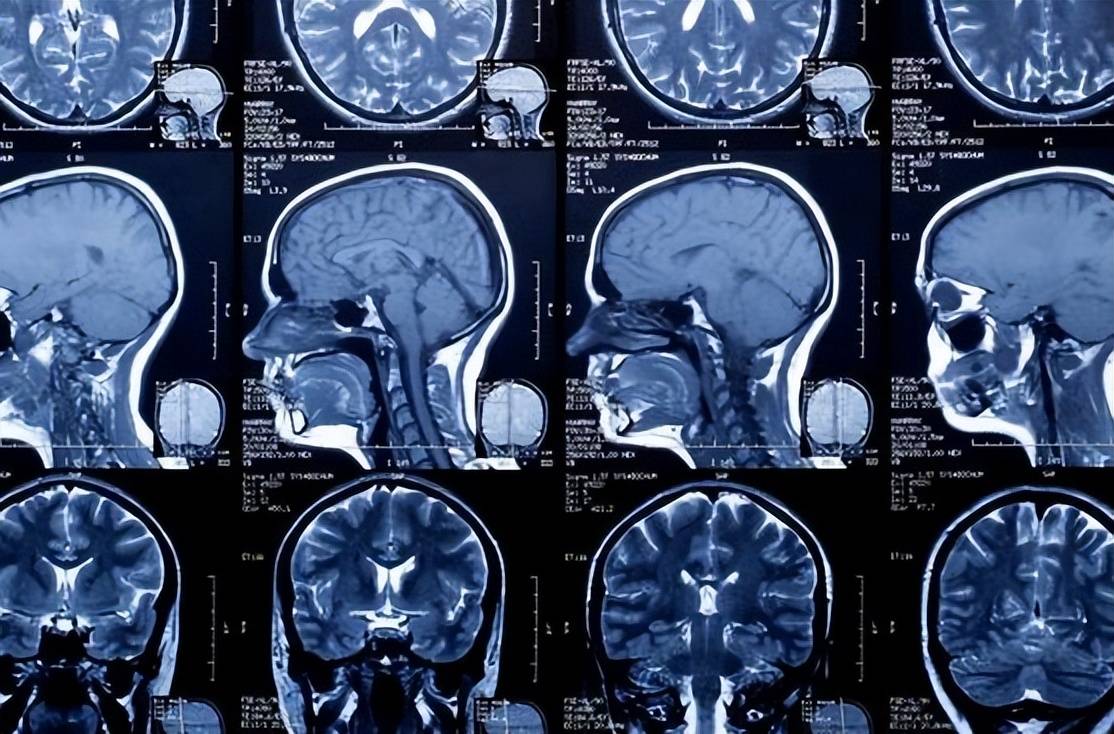

磁共振成像(MRI)是高分辨率成像技术的重要组成部分,在医学影像诊断中具有广泛应用。近年来,中国科学家在MRI领域取得了多项创新成果。例如,中国科学院深圳先进技术研究院的科研团队,成功开发出高场强MRI系统,将磁场强度提高至7T,实现了更高分辨率的成像。这项技术在神经科学和心血管疾病等领域的研究中具有广泛应用前景。

除了改进硬件和算法,中国的科技工作者还积极开展MRI技术在不同领域的应用研究。例如,在肿瘤诊断方面,中国的科研人员提出了一种基于MRI的肿瘤成像技术,能够更准确地评估肿瘤的恶性程度和扩散性。这项技术利用多参数成像和功能性MRI等先进方法,实现了对肿瘤组织的全面分析。此外,在神经科学领域,中国的科学家们利用MRI技术,研究人脑的结构和功能连接,为解析人类大脑的奥秘做出了积极贡献。

中国科学家还开展了多模态磁共振成像的研究。传统磁共振成像通常只能提供结构信息,无法获取功能性信息。而多模态磁共振成像结合了传统磁共振技术和其他成像技术,如功能性磁共振成像、扩散张量成像等,可以同时获得结构和功能性信息,为医生提供更全面的诊断依据。中国科学家在这方面的研究成果,为疾病诊断和治疗提供了更准确的方式。